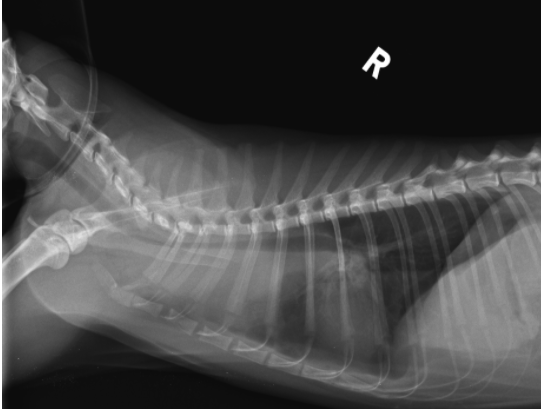

貓 淋巴癌 胸水 胸腔前縱膈腔腫瘤 腹腔淋巴結腫大 化療 不是感冒 首頁 病例分享 腫瘤科 貓 淋巴癌 胸水 胸腔前縱膈腔腫瘤 腹腔淋巴結腫大 化療 不是感冒 1歲已絕育母貓,就診前一周精神食慾下降、咳嗽,在他院診斷感冒治療無效而就醫。 經急診醫師檢查發現有嚴重胸水、前縱膈團塊、腹腔淋巴結腫大。 排除心臟病、白血病等等鑑別診斷後採樣確診為貓咪的淋巴癌。 雖然淋巴癌的治癒率非常低,但對化療有良好反應的機率很高,於是後續開始化療計畫。 影像檢查結果 嚴重胸水 抽完胸水後發現前縱膈腔團塊. 腹腔內淋巴結多發腫大 病理切片: 箭頭所指處為有絲分裂中的淋巴癌細胞